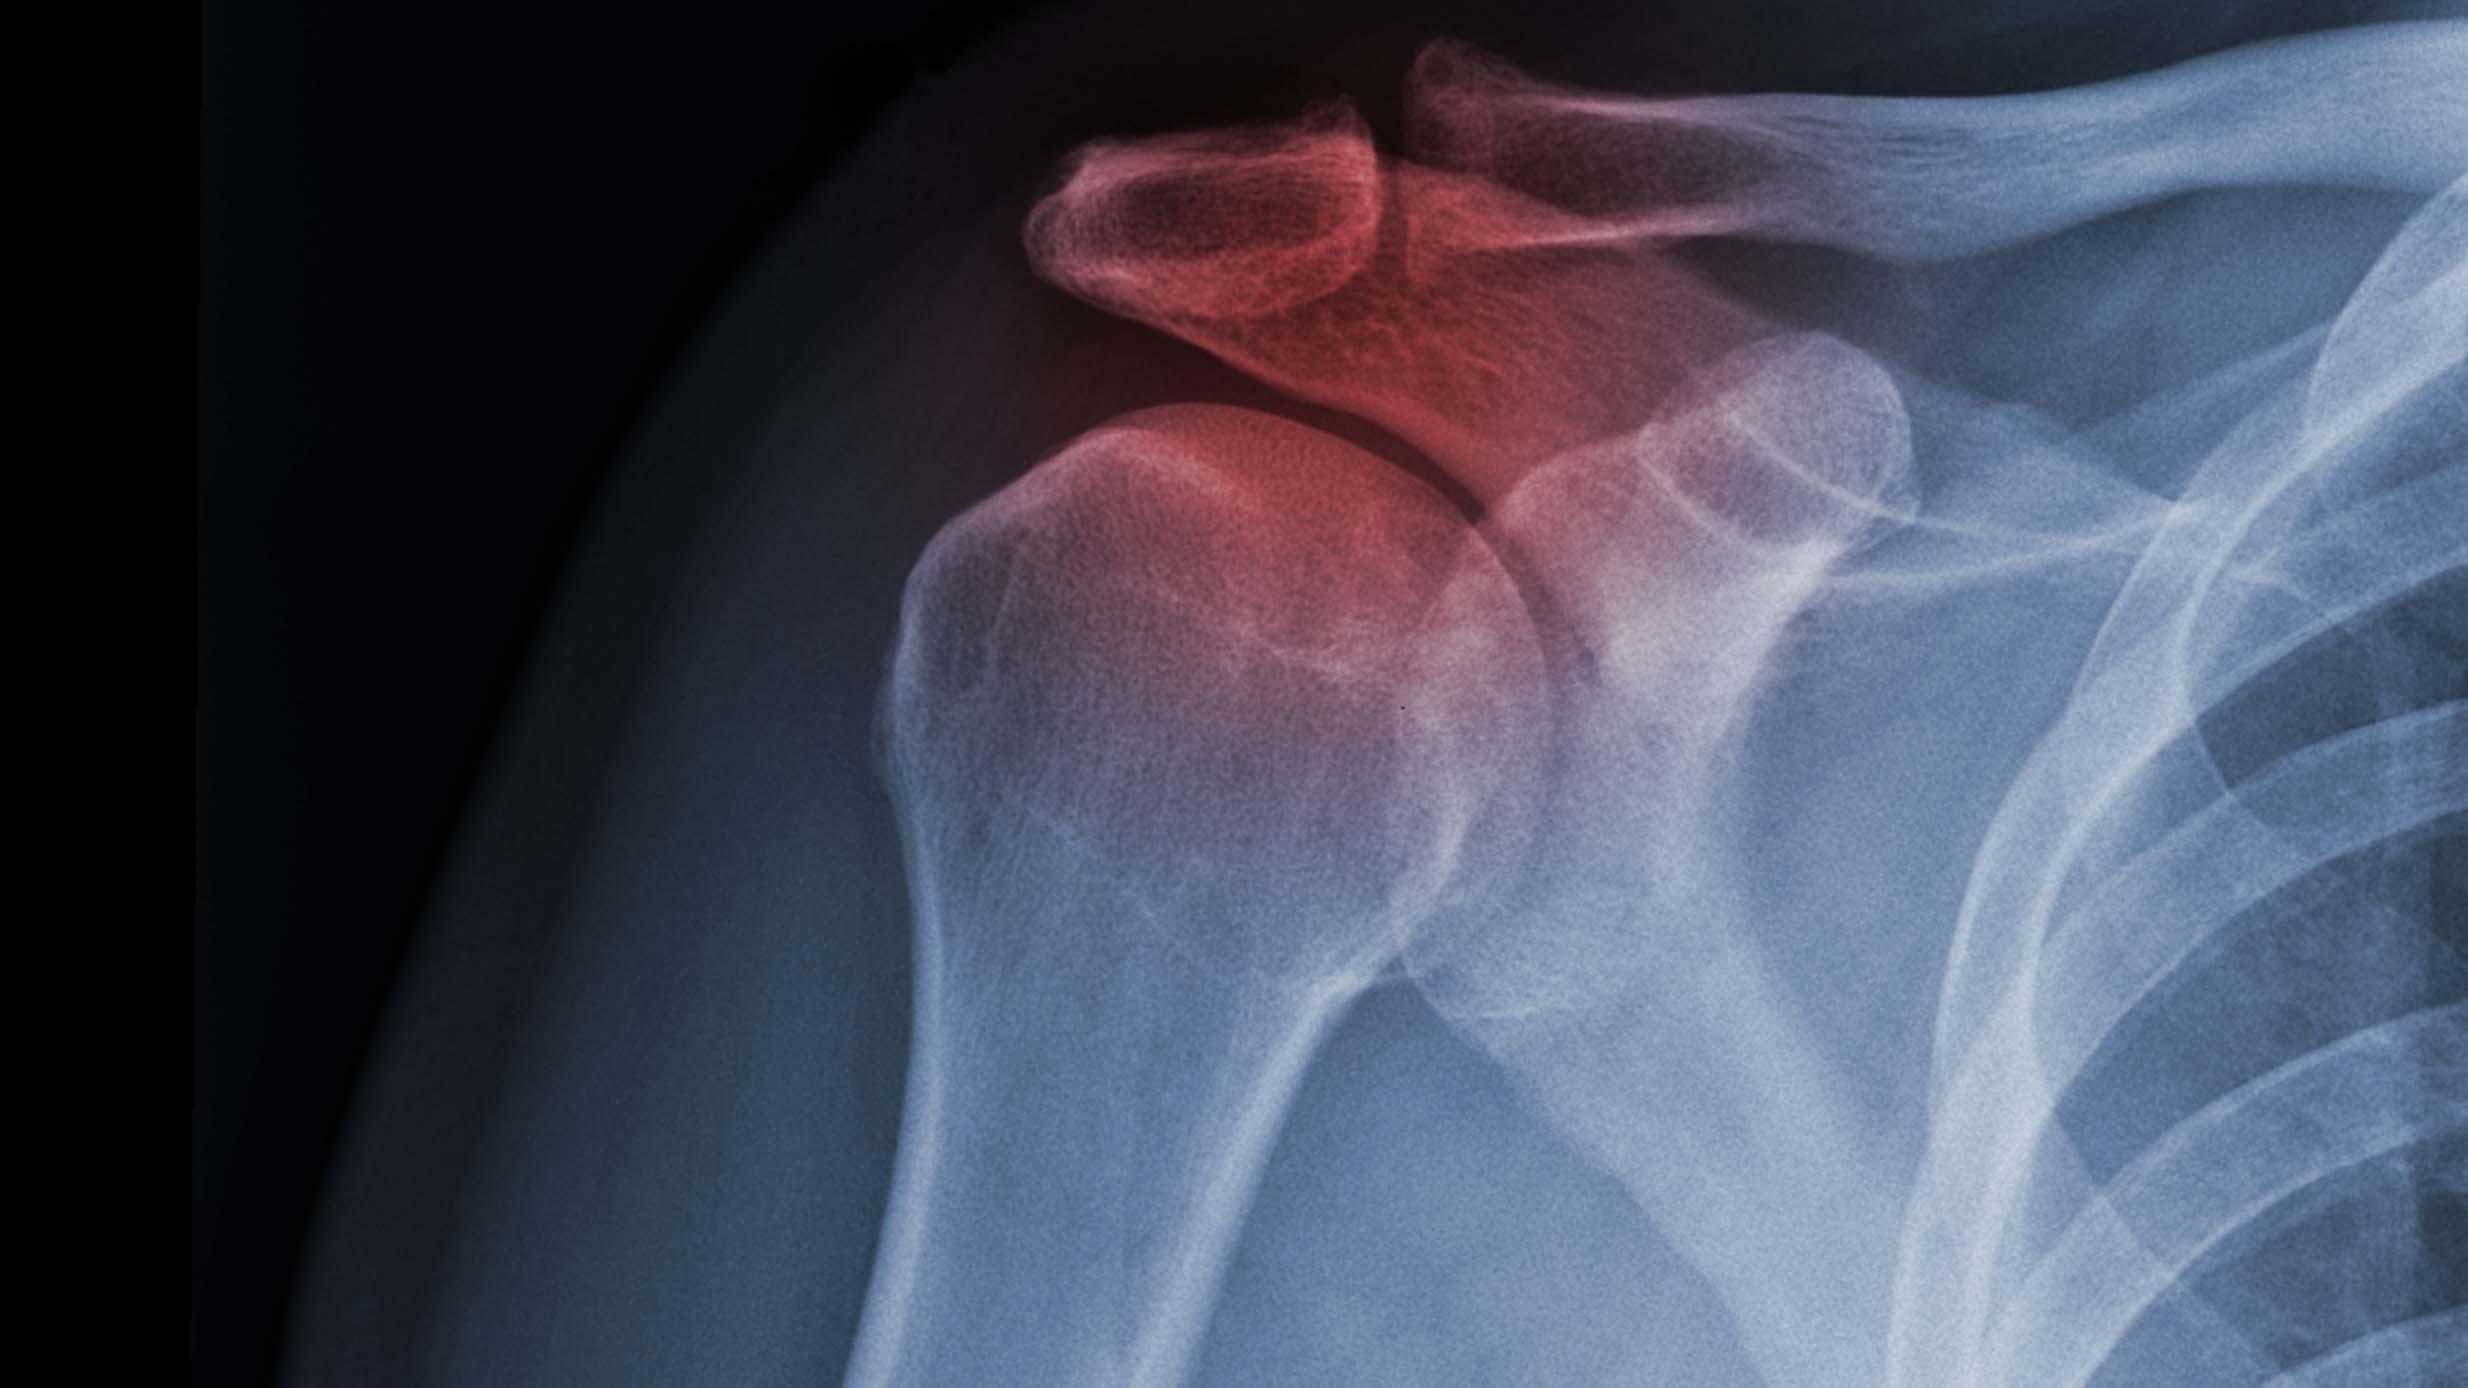

Ved frossen skulder ses inflammation af ledkapslen og synovia, som giver invaliderende smerter og bevægelsesindskrænkning. Tilstanden kan være idiopatisk eller sekundær til traumer eller kirurgi og rammer op til 2% af befolkningen. Hovedparten af patienterne oplever spontan lindring, men vedvarende invaliderende symptomer ses hos ca. 10%, og op til 40% har residualsymptomer fire år efter debut. Nyt randomiseret engelsk studie sammenligner effekt af tre typer interventioner: artroskopisk løsning af adhærencer i fuld bedøvelse, manipulation i fuld bedøvelse (begge behandlinger fulgt op af fysioterapi) og tidlig målrettet formaliseret fysioterapi ledsaget af steroidinjektion. Forfatterne inkluderede 503 patienter i de tre behandlingsarme, som blev fulgt i et år, hvor det primære udfald var forbedring i Oxford Shoulder Score. De konkluderer, at der ikke var store forskelle mellem de tre behandlingsarme, men at manipulationen i generel anæstesi var mest kost-effektiv.